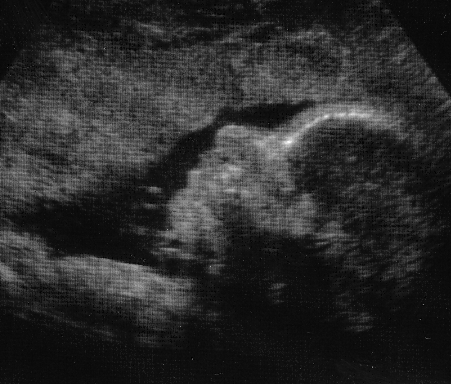

Closeup of the baby

Pregnancy at 16 Weeks

What a difference 6 weeks make! Looks like

the baby has my nose and Kim's eyes.